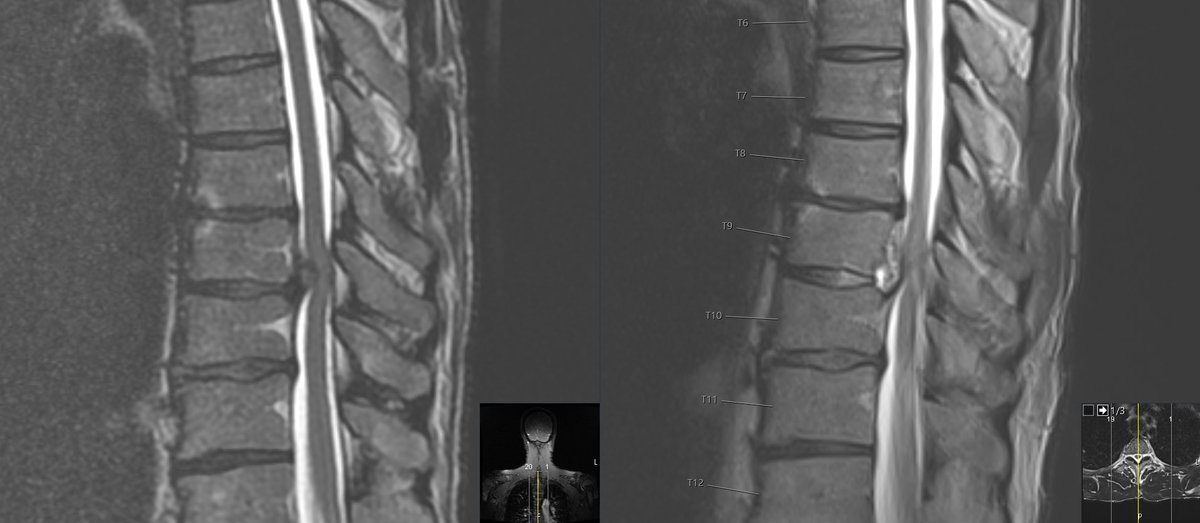

Ventral thoracic intradural tumors can be safely reached from a posterior approach with release of the dentate ligaments and drilling more of the facets. @emoryhealthcare @EmoryNeurosurg @spinesection